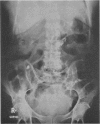

The importance of preoperative diagnosis or suspicion of obturator hernia is stressed. In this radiology may be of help.

Images in this article